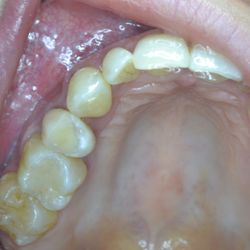

Ο κάτω γομφίος σε αυτή την νεαρή ασθενή έχει απονευρωθεί.

Για να εξασφαλίσουμε την καλή πρόγνωση του δοντιού και ταυτόχρονα την προστασία του από πιθανό κάταγμα, αποφασίστηκε η τοποθέτηση ενός επενθέτου εργαστηριακής σύνθετης ρητίνης.

Η διαδικασία ολοκληρώθηκε σε 2 ραντεβού, ενώ ο τροχισμός του δοντιού διατηρήθηκε στο ελάχιστο δυνατό.

Η εναλλακτική λύση θα ήταν να τροχιστεί εντελώς το δόντι και να τοποθετηθεί μια στεφάνη, οδηγώντας όμως έτσι σε αφαίρεση μεγάλης ποσότητας οδοντικής ουσίας.